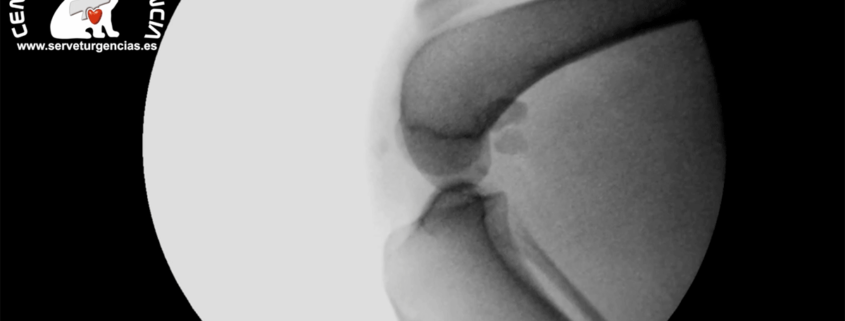

TTA con fluoroscopio intraoperatoria. El avance tuberosidad tibial se consiguió mediante el implante de una cuña de titanio MMP